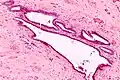

Endosalpingiosis is diagnosed by a pathologist on excision (e.g. biopsy).

It is characterized by cysts with tubal-type epithelium (e.g. ciliated epithelium) surrounded by a fibrous stroma. It is not often associated with hemorrhage.

Endosalpingiosis is occasionally found in lymph nodes, and may be misinterpreted as an adenocarcinoma metastasis.[6]